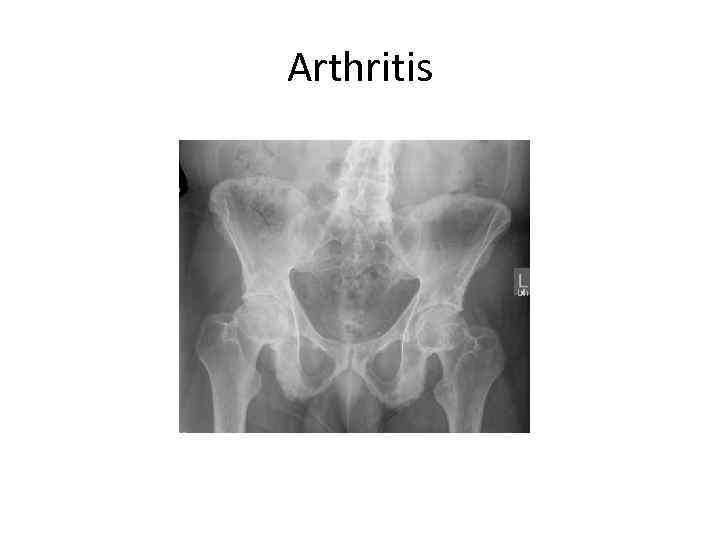

Arthritis